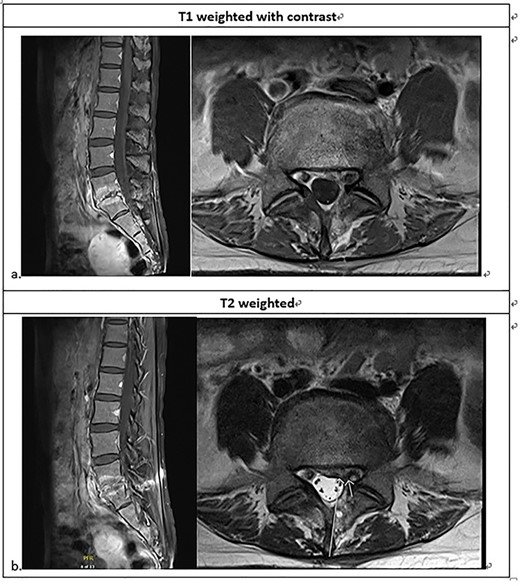

Lumbarsacral spine MRI (a) posterior bulging disc at L5-S1; extruding disc at the left subarticular zone of the left L5-S1, with compression of the left S1 nerve root; neural foraminal stenosis at left L5-S1; increased enhancement at L5-S1 related to the spondylitis change; (b) The arrow point at neural foraminal stenosis at left L5-S1.

She was referred to our institute for spine consultation at 3 months after surgery. On physical examination, she had numbness at the left S1 dermatome and saddle anesthesia. Visual analog scale was 8 when admission. The straight leg raising test was bilaterally negative. She had no lower extremity weakness. Contrast-enhanced lumbar-spine MRI showed posterior bulging disc with decreased disc space and endplate changes of L5-S1. We suspected an extruding disc in the left subarticular zone at left L5-S1, compressing the left S1 nerve root. There was increased enhancement at L5-S1, but the paraspinal soft tissue was clear without enhancement (Fig. 1).

Follow-up MRI after 1 month of antibiotics showed little change at the L5-S1 intervertebral disc and adjacent endplates, consistent with partially treated spondylodiscitis. There was also less compression of the left S1 nerve root (Fig. 3).

Lumbosacral MRI ~3 weeks after the intervention; less enhancement compared to the previous MRI at the L5-S1 intervertebral disc with adjacent endplates, consistent with spondylodiscitis; less compression of the left S1 nerve root.